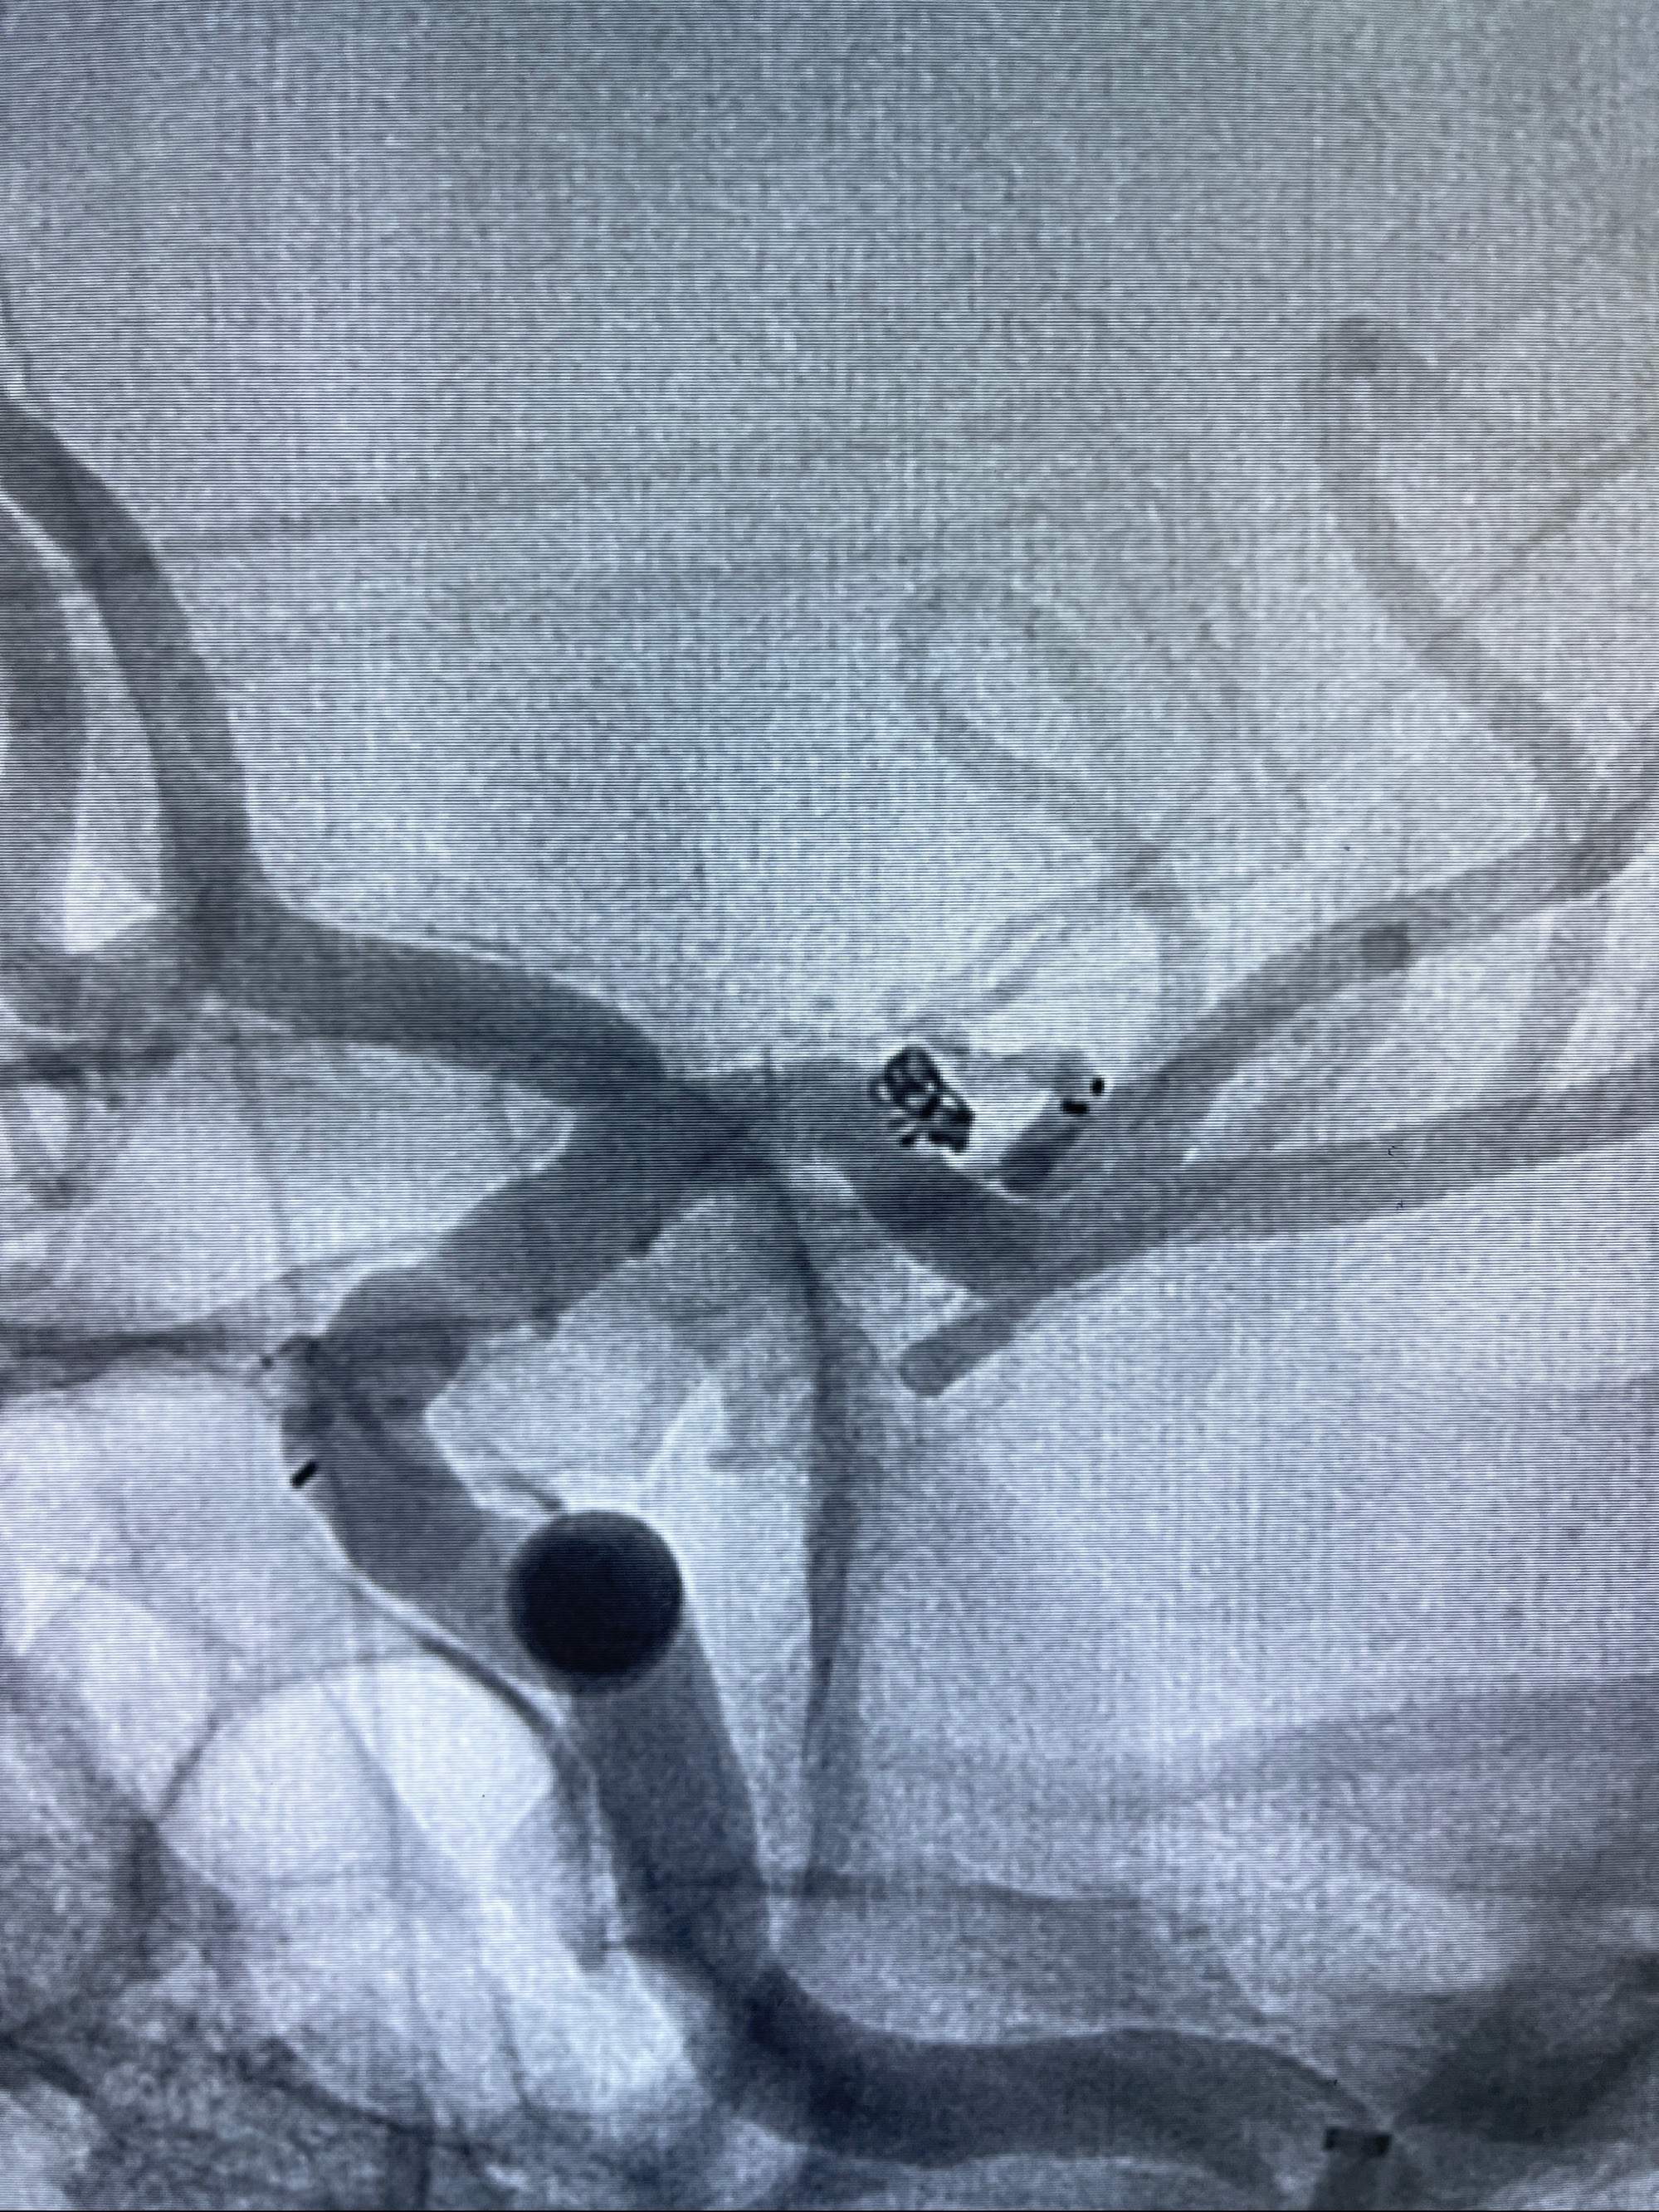

2023-08-14DSA:

左侧大脑中动脉动脉瘤,约2.6-2.8-3.4-2mm大小(瘤颈部、瘤体部、瘤高)

1.左侧大脑中动脉动脉瘤,约2.6-2.8-3.4-2mm大小(瘤颈部、瘤体部、瘤高)

2.外科手术夹闭or介入支架辅助栓塞